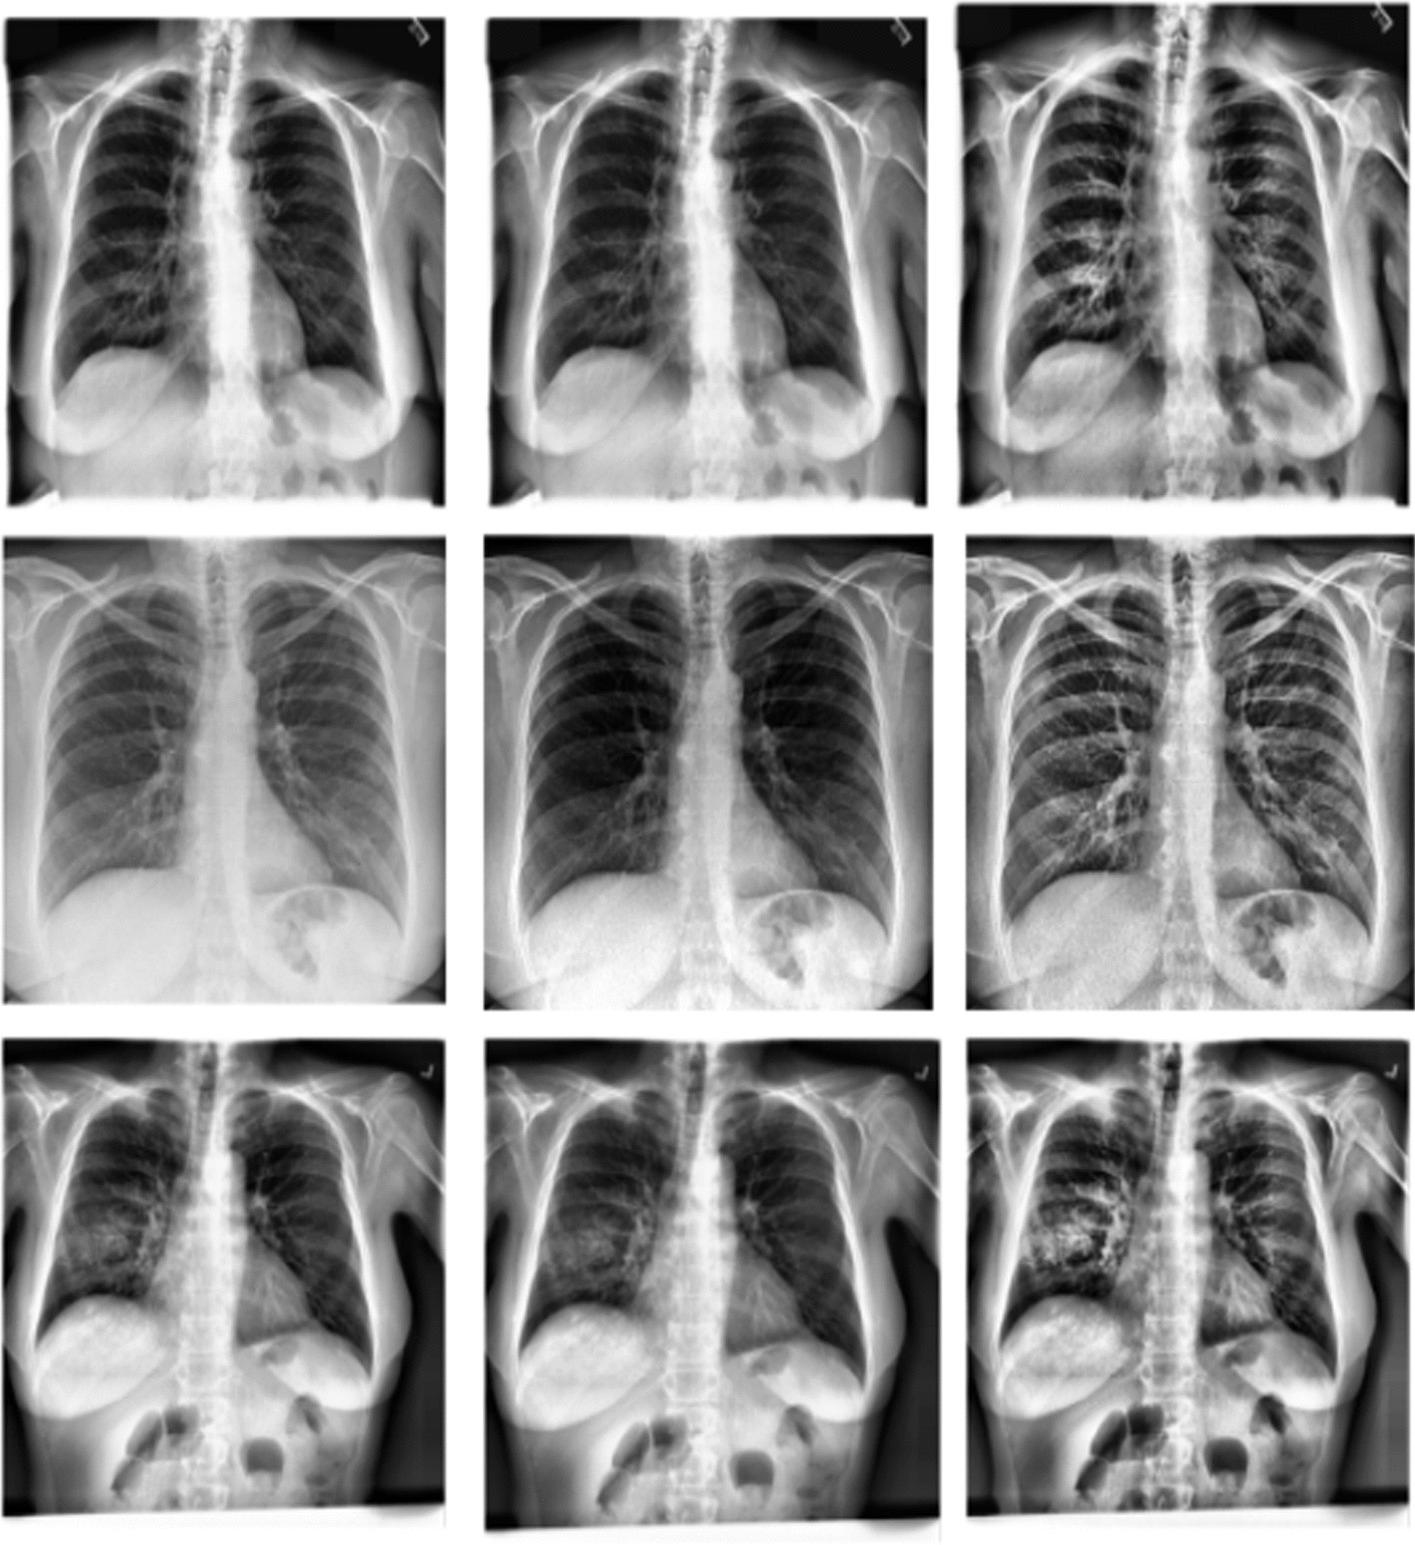

COVID-19 detection from chest X-ray images using CLAHE-YCrCb, LBP, and machine learning algorithms.

COVID-19 is a disease that caused a contagious respiratory ailment that killed and infected hundreds of millions. It is necessary to develop a computer-based tool that is fast, precise, and inexpensive to detect COVID-19 efficiently. Recent studies revealed that machine learning and deep learning models accurately detect COVID-19 using chest X-ray (CXR) images. However, they exhibit notable limitations, such as a large amount of data to train, larger feature vector sizes, enormous trainable parameters, expensive computational resources (GPUs), and longer run-time.

In this study, we proposed a new approach to address some of the above-mentioned limitations. The proposed model involves the following steps: First, we use contrast limited adaptive histogram equalization (CLAHE) to enhance the contrast of CXR images. The resulting images are converted from CLAHE to YCrCb color space. We estimate reflectance from chrominance using the Illumination-Reflectance model. Finally, we use a normalized local binary patterns histogram generated from reflectance (Cr) and YCb as the classification feature vector. Decision tree, Naive Bayes, support vector machine, K-nearest neighbor, and logistic regression were used as the classification algorithms. The performance evaluation on the test set indicates that the proposed approach is superior, with accuracy rates of 99.01%, 100%, and 98.46% across three different datasets, respectively. Naive Bayes, a probabilistic machine learning algorithm, emerged as the most resilient.